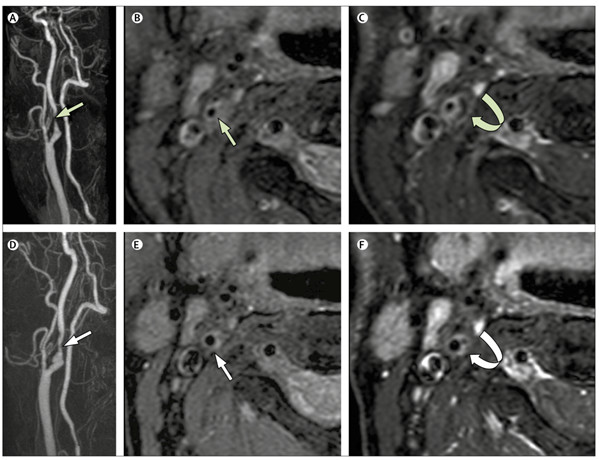

图9 他汀治疗后斑块减小[9]。患者为73岁男性患者,从2015年7月(a/b/c)至2017年7月(d/e/f)期间接受他汀类药物治疗后斑块消退,LRNC减少。a/d,MRA;b/e,T1序列;c/f,T1增强压脂序列。